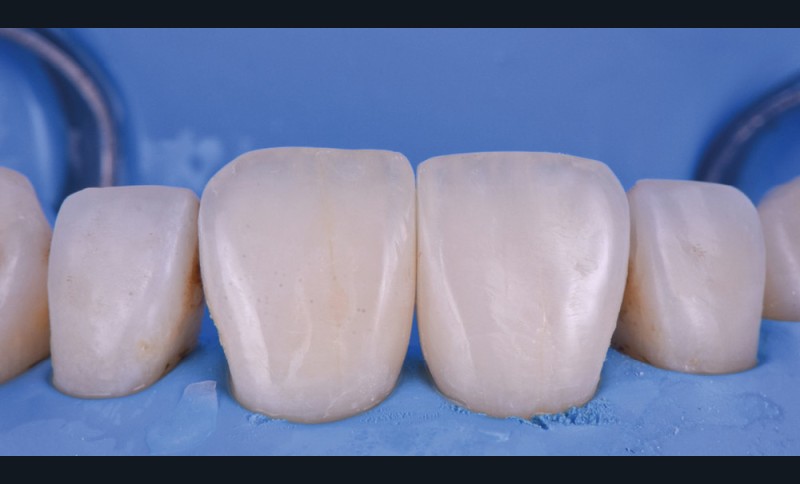

La fermeture des triangles noirs en technique directe avec des résines composites offre une alternative très favorable avec une approche non invasive, esthétique, un coût réduit et une possibilité de réintervention aisée. Plusieurs méthodes ont été proposées : réalisation à main levée sans matrice (à proscrire), avec bande de matrice transparente plate ou galbée, avec matrice postérieure customisée et utilisée verticalement… Il faut bien comprendre qu’aucun coin en bois ou plastique ne pourra être employé pour stabiliser cette matrice, car il empêcherait la création d’un profil d’émergence anatomique convexe en induisant une déformation concave de la matrice à sa base.